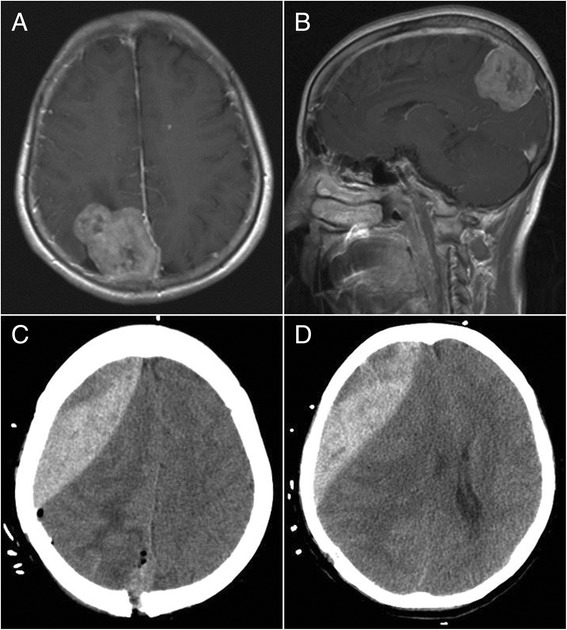

Fig. 2.

Ipsilateral remote hemorrhage in case 2. a, b Preoperative-enhanced MRI revealed a meningioma at the top right of the sagittal sinus. c, d CT showed an epidural hematoma in front of the surgical field after the tumor resection